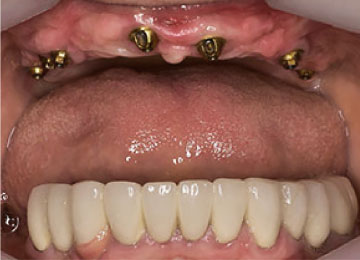

Имплантация зубов: фото "До" и "После"

All-on-4

All-on-6